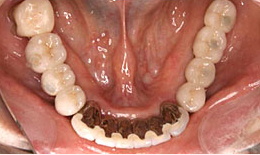

インプラント症例(4) 68歳 女性

治療後

下顎

保存困難な歯を抜歯後、インプラントを5本埋め込み、セラミックスクラウンを被せた